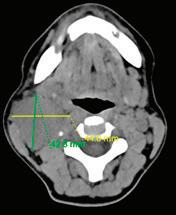

Случай 3: Метастатична шийна

жена, А.С., постъпва с плътна, неболезнена, прогресивно нарастваща формация на шията вдясно, ниво III, която причинява и лекостепенна дисфагия. Липсват оплаквания от страна на горните дихателни пътища, температура или нощно изпотяване. Ехографското изследване показва хомо

контролна КТ, с данни за лимфогенна шийна диссеминация двустрнно. Извършена радикална

шийна лимфна дисекция двустранно, с хистологичен резултат метастази от умерено диференциран невроговяващ плоскоклетъчен карцином. Три месеца по-късно при проведен контролен ПЕТ/КТ данни за зави -

шена метаболитна активност на ляв шиен

лимфен възел ниво II. Предприе се ексцизия

на същия с хистологичен резултат масив -

на метастаза от невроговяващ плоскоклетъчен карцином. Три месеца по-късно проведен повторен контролен ПЕТ/КТ, от който са